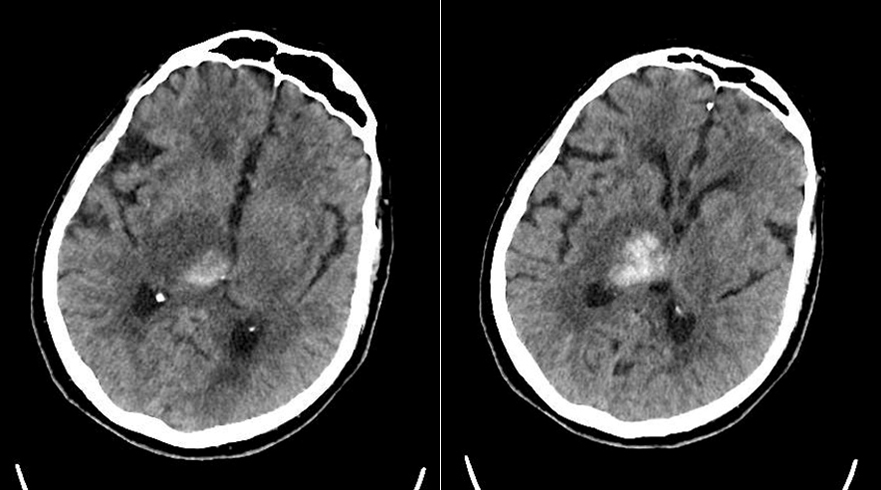

Le type d’hémianopsie est très important car il permet de localiser une atteinte neurologique, en connaissant le trajet des voies optiques.

Cette question supposait d’avoir bien en tête le schéma des voies optiques, et d’avoir des repères sur les principaux territoires vasculaires cérébraux et l’atteinte clinique associée. Il bien mentionné par le CEN que l’hémianopsie latérale homonyme gauche peut se voir dans un AVC sylvien superficiel droit.